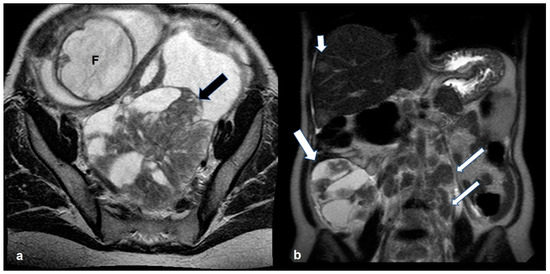

2.5. Pregnancy

2.5.2. Decidualized Endometrioma

2.5.3. Epithelial Ovarian Cancer